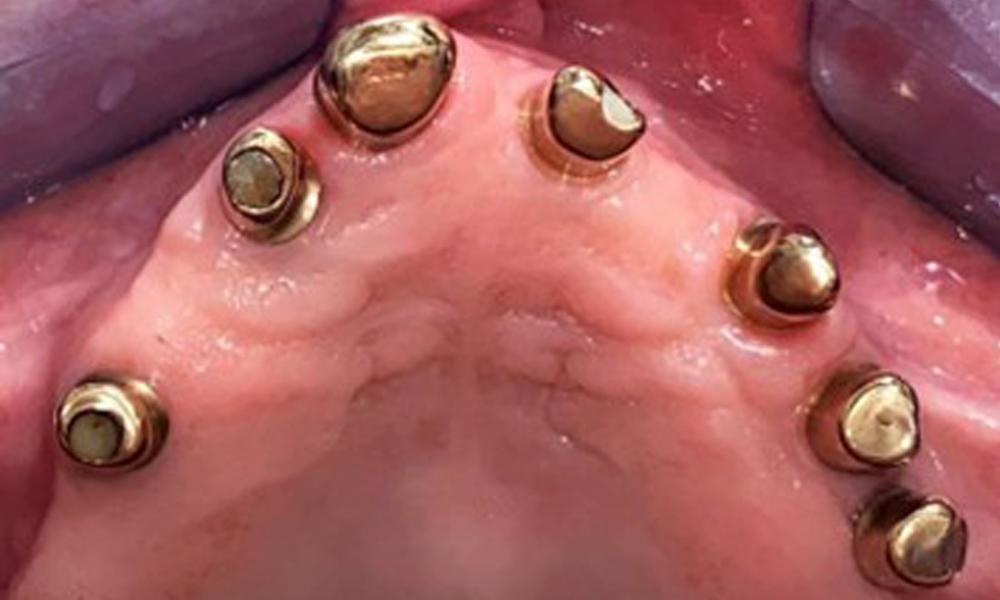

Die Patientin wurde vor über 25 Jahren mit einer kombinierten herausnehmbare Implantat-Teleskopprothese im Oberkiefer versorgt (Abb. 1, Abb. 2, Abb. 3) und ist sehr glücklich über ihren Zahnersatz. Im Unterkiefer hat die Patientin einen suffizienten festsitzenden Zahnersatz. (Abb. 4)

Der dentale Befund stellt sich wie folgt dar: Kombinierte herausnehmbare Implantat- und zahngetragene Teleskoparbeit auf Implantaten 15, 13, 21, 23, 24, 25 und Zahn 11 (Abb. 1, Abb. 2, Abb. 3). Im Unterkiefer ist die Patientin mit einem festsitzenden Zahnersatz versorgt. 37–34 sowie 45–47 haben suffiziente Brücken (Abb. 4). Kronenränder sind intakt, aktive kariöse Läsionen sind nicht vorhanden. An Zahn 43 zeigt sich eine Compositefüllung mit Randspalt. Im Unterkiefer liegen Rezessionen mit freiliegender Wurzeloberfläche zwischen 1 – 3 mm vor. Dies trifft auch für 11 zu.